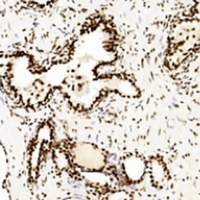

IHC (Immunohiostchemistry)

(Immunohistochemical analysis of CREB staining in human prostate cancer formalin fixed paraffin embedded tissue section. The section was pre-treated using heat mediated antigen retrieval with sodium citrate buffer (pH 6.0). The section was then incubated with the antibody at room temperature and detected using an HRP conjugated compact polymer system. DAB was used as the chromogen. The section was then counterstained with haematoxylin and mounted with DPX.)